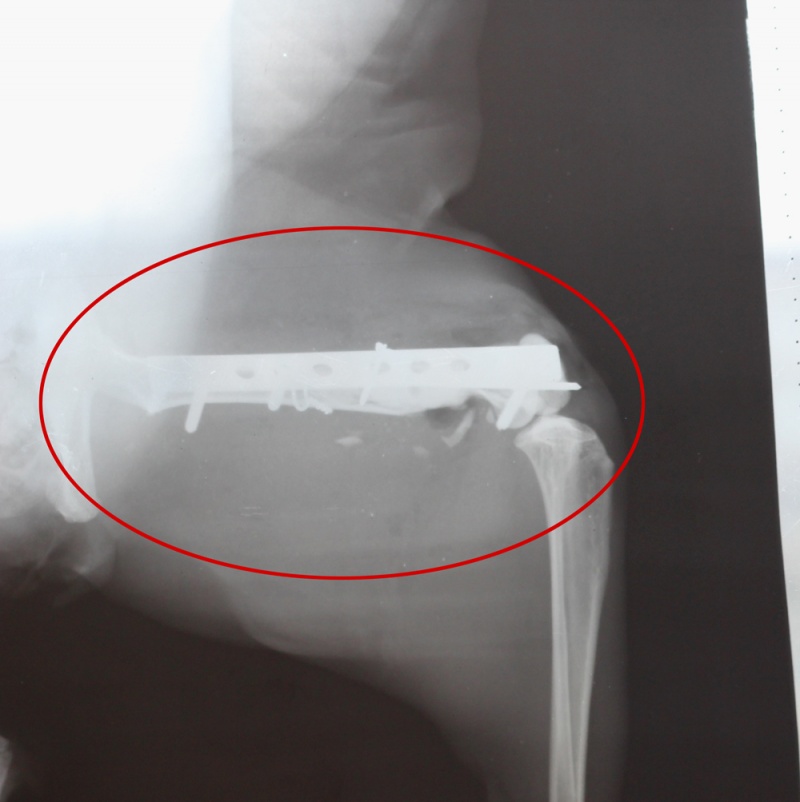

В какой клинике оперируетесь? Что-то дороговато, мне кажется. А почему оперируют в 2 этапа?В Центральной ветеринарной клинике, хирург Тетерин О.А. Сумму в 7 т.р. нам сказали сегодня, предварительно. Завтра я позвоню и узнаю точно, у самого лечащего врача.

Большая просьба к Вам - выложите, пожалуйста, лист приема из клиники с дигнозом и рекомендациями врача.Вот, все, что есть.